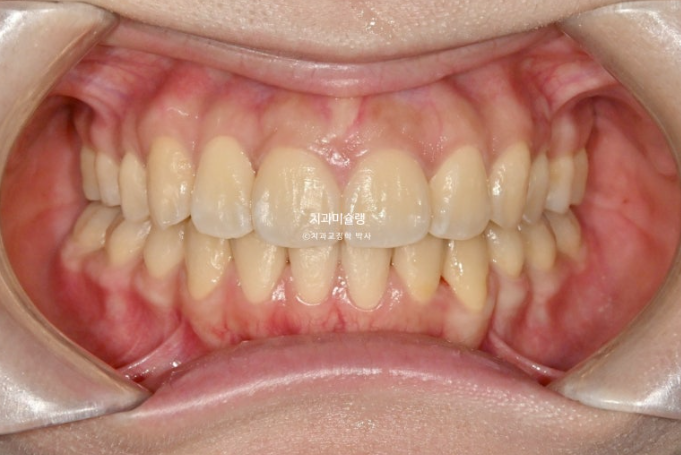

26.01

중심선은 일치하고

어금니 교합은 물샐틈 없는 1급 교합관계를 보이며 쫀쫀하죠 (?)

이제 전후 비교 보여드릴게요

재제작은 총 2회를 진행했고

총 치료기간은 2년 3개월 입니다.

개방교합이 해소되어 잘 물립니다

중심선 불일치는 해결이 되었습니다.

교합이 좋습니다.

스마일라인은 아랫입술과 평행하여 조화롭습니다.